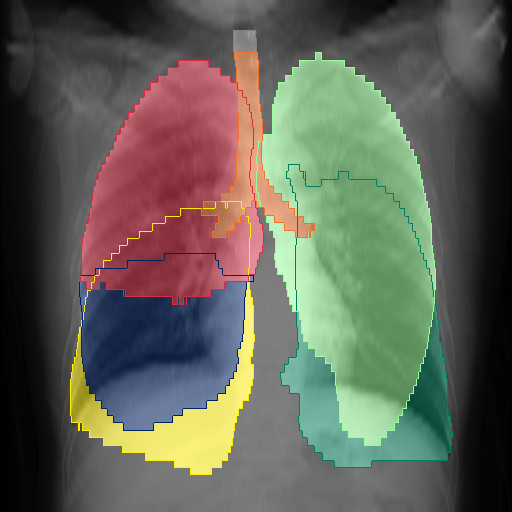

We show qualitative results for frontal projections in Fig. 2. We show a subset of classes belonging to the supercategories lungs, vascular systems, bones, and abdomen/digestive system. The predictions show minor deviations at the boundaries of the individual classes of the respiratory and vasculature system, while some inaccuracies become visible in the abdominal area. The qualitative results for the lateral projections are displayed in Fig. 2. Akin to the frontal view, the predictions show smoother borders but align with the ground truth. Apart from this, the segmentations provide matching insights on the thoracic anatomy with a slight deviation from the ground truth for both frontal and lateral views.

We display qualitative results in Fig. 3. The annotators tend to be content with most annotations. There are edits at the extensions of the esophagus, trachea, and aorta and corrections of the lower ribs. There is little consensus for classes in the abdominal area, such as the stomach, as seen on the right of Fig. 3 . In contrast, the annotators often align for bone classes.